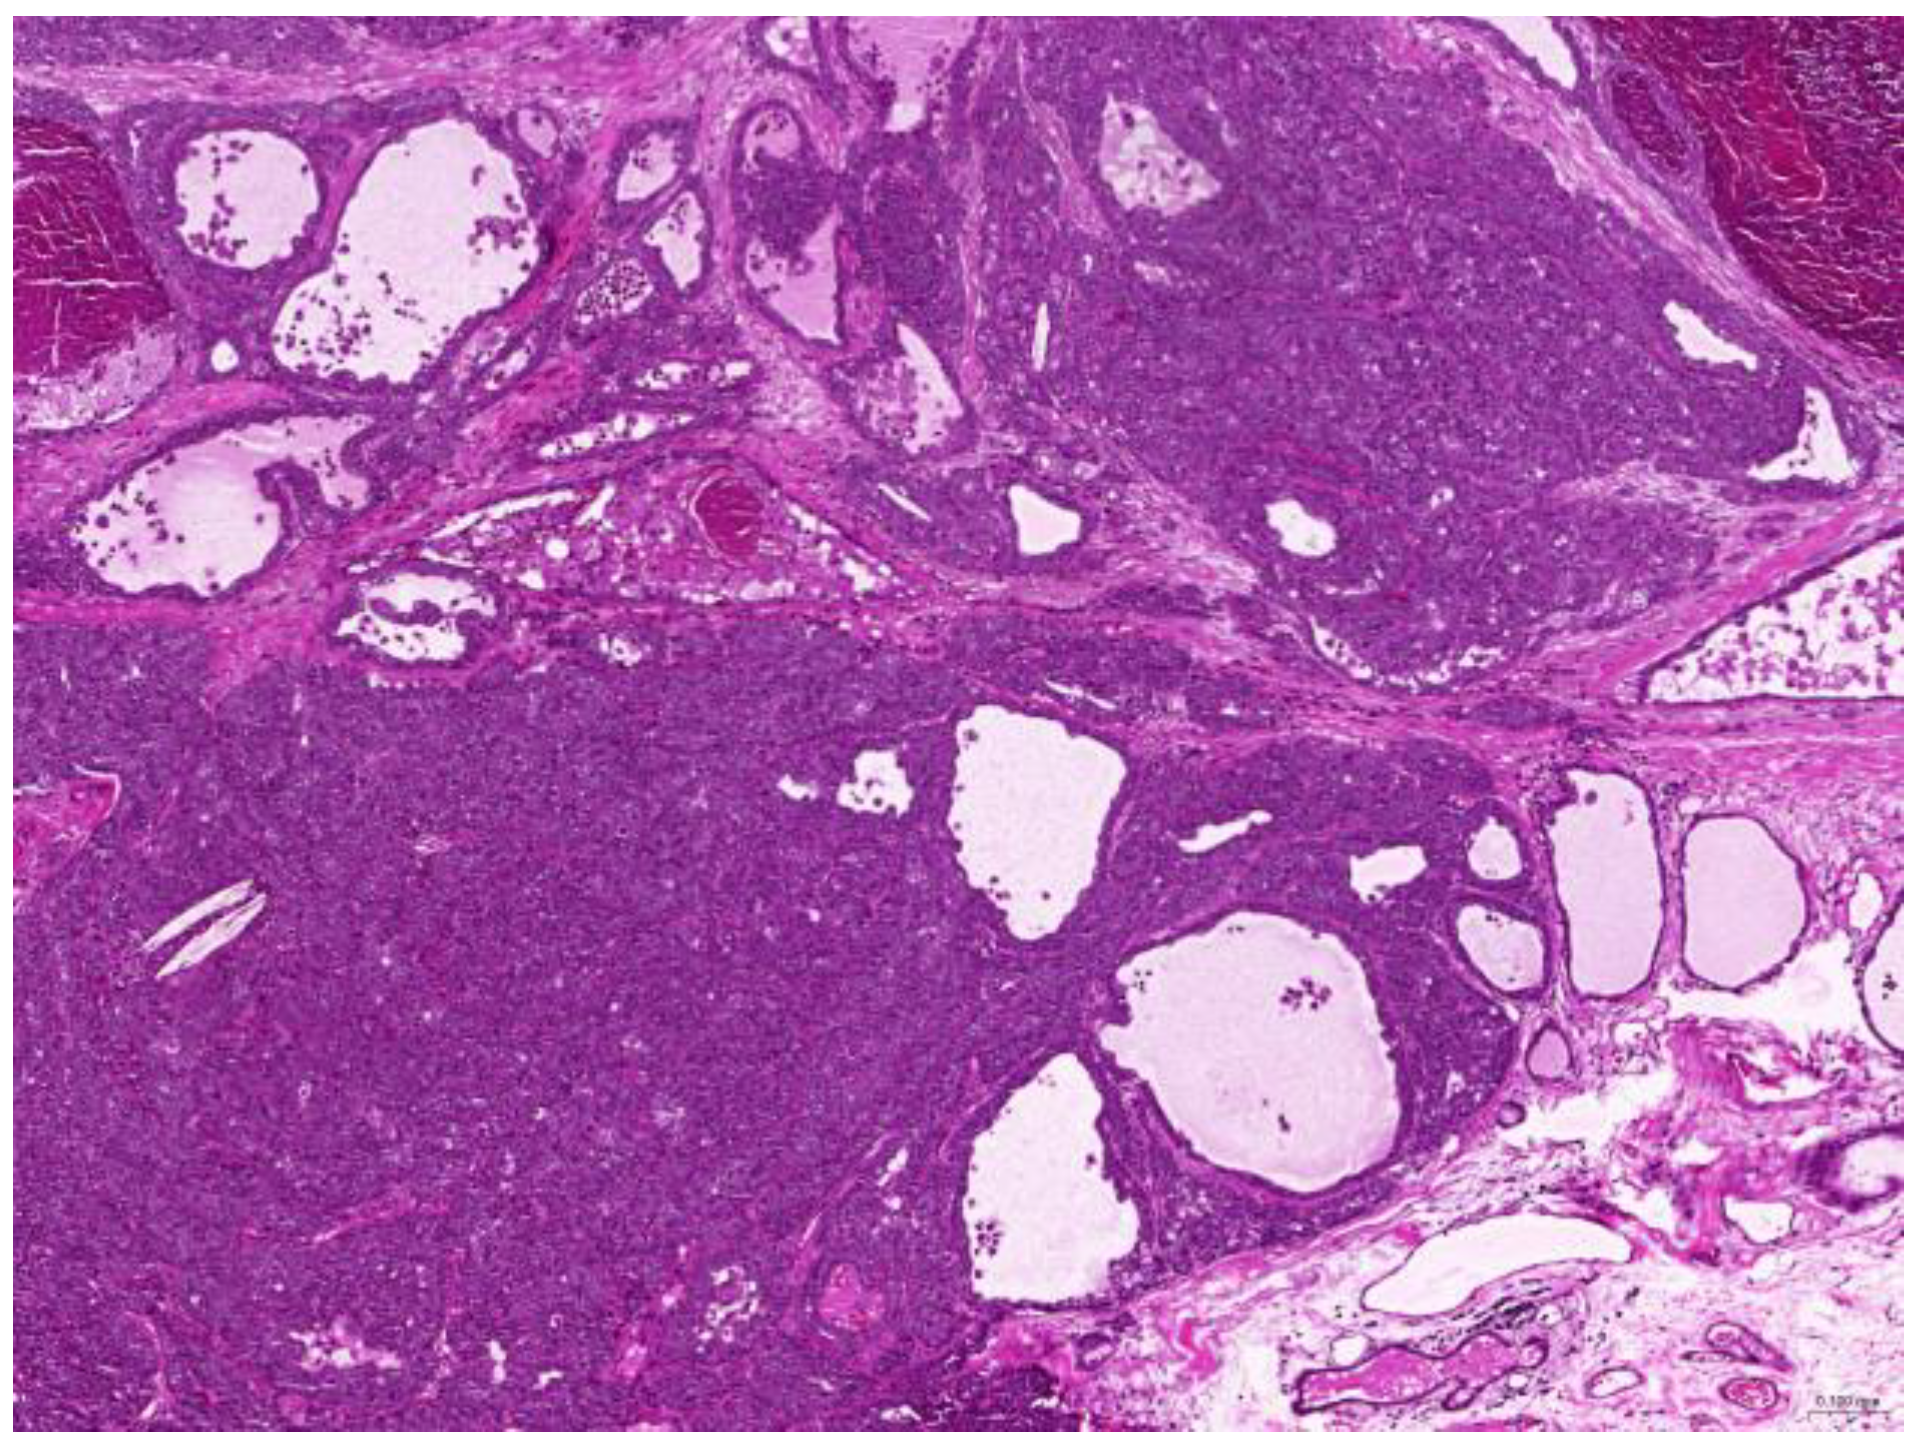

Thirty-six biopsy specimens were taken from the reproductive systems of 22 females and two males (a female-to-male ratio of 11:1). All of the females were intact, and 32 diagnoses were obtained from these 22 females. The median age of the affected females was 71 (20–132) months. The most common diagnoses were uterine adenocarcinoma (50%, 16/32) (Figure 6), followed by endometrial cystic hyperplasia (15.6%, 5/32), uterine adenomyosis (12.5%, 4/32), uterine leiomyoma (6.25%, 2/32), and luteoma (6.25%, 2/32). The median age of the females with uterine adenocarcinoma was 82 (42–132) months. From the two male rabbits, four diagnoses affecting the reproductive system were obtained. Both of these males were intact. The median age of the affected males was 113.5 (109–118) months. The most common diagnosis was interstitial cell tumor (50%, 2/4), followed by seminoma (25%, 1/4) and testicular atrophy (25%, 1/4).

Figure 6. Uterine adenocarcinoma. The neoplasm effaces the original uterine structure (scale bar = 500 µm). Hematoxylin and eosin staining.